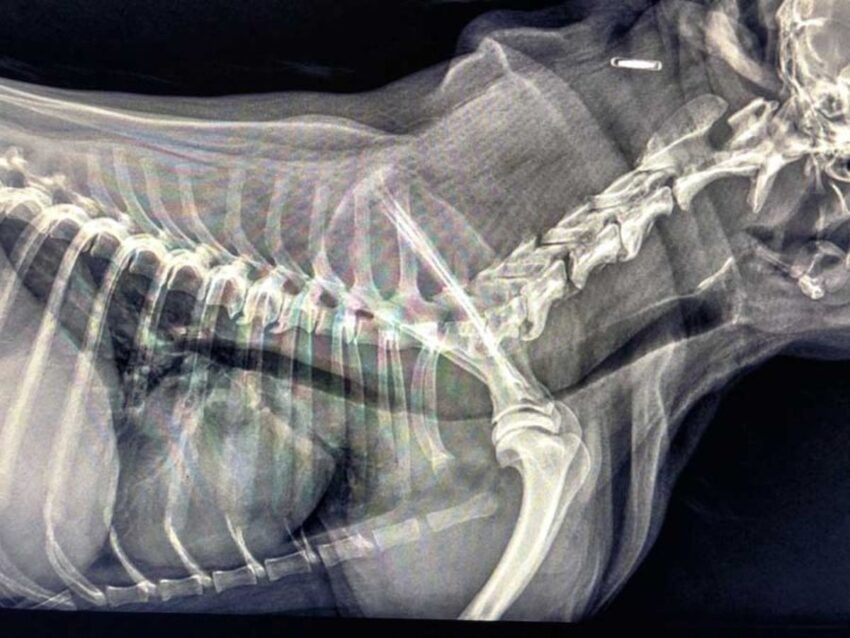

Źródło: https://wetgliwice.pl/ Zapadanie tchawicy u psów (TCS-Tracheal Collapse Syndrome) Zapadanie tchawicy u psów (TCS-Tracheal Collapse Syndrome) jest przewlekłą chorobą układu oddechowego obserwowaną głównie u raz małych i miniaturowych (Yorkshire terrier, Szpic miniaturowy, Chihuahua). Choroba ta polega na „zapaści” tchawicy co w znacznym stopniu ogranicza jej drożność. Odnotowuje się dwa procesy przyczyniające się do rozwoju tej choroby….